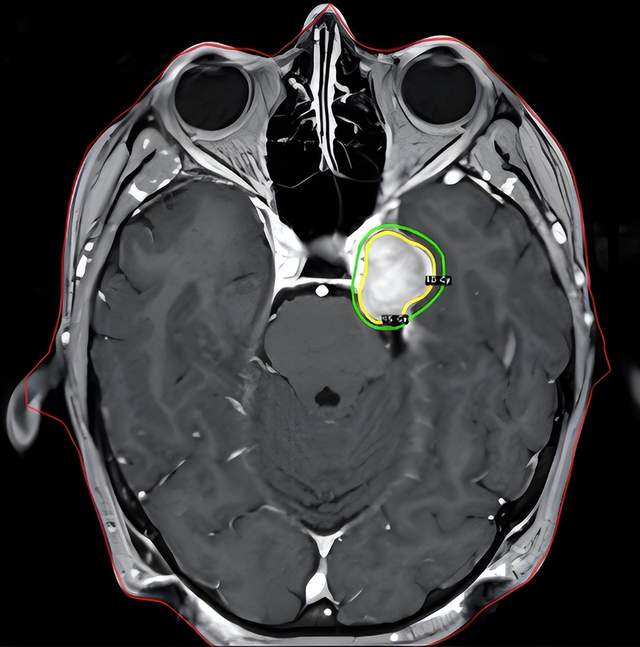

脑膜瘤一般都是良性肿瘤.这个53岁女病人因头痛发现脑部长了两 - 抖音